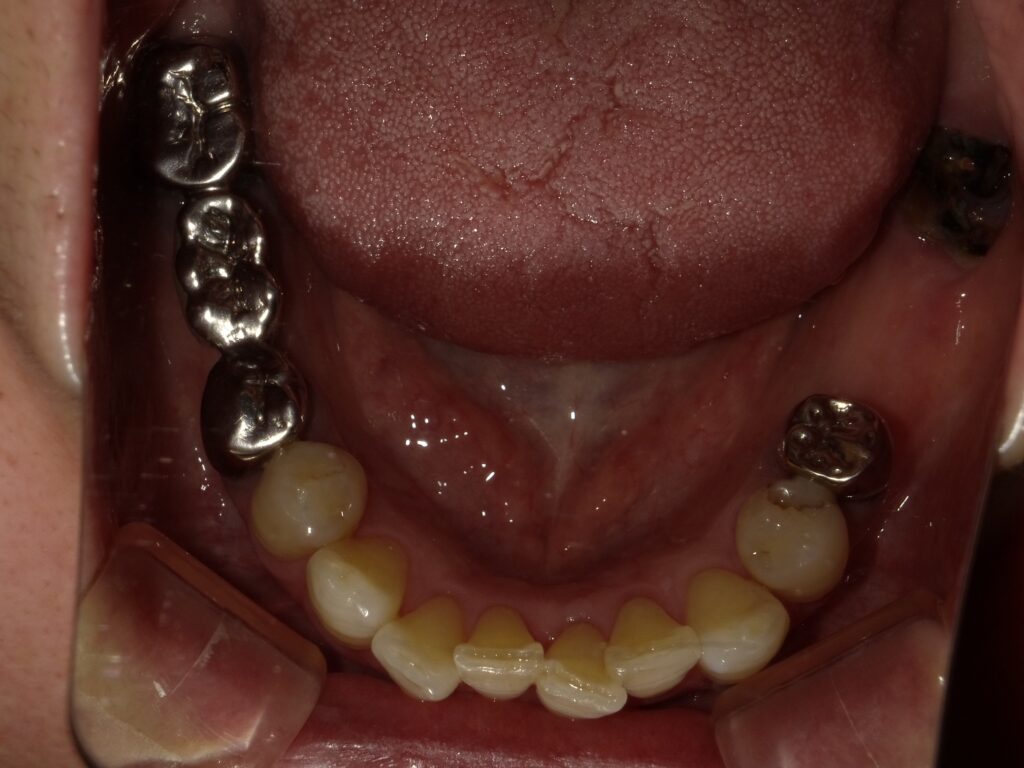

BEFORE

AFTER

主訴

全体的に見た目を綺麗にしたい。奥歯でしっかり噛みたい。

診断名・主な症状

臼歯部欠損

年齢

70歳

治療内容

インプラント埋入(右上4・6,左上4・6,右下6,左下6)

ジルコニアBr(右上3―左上3)

ジルコニア(右下5,左下5)

治療期間/

通院回数

インプラント 1年5ヶ月/13回

ジルコニアBr、ジルコニアクラウン 3ヶ月/10回

費用

インプラント: 2,552,000円

その他治療: 640,000円

合計 3,192,000円

*いずれも税込